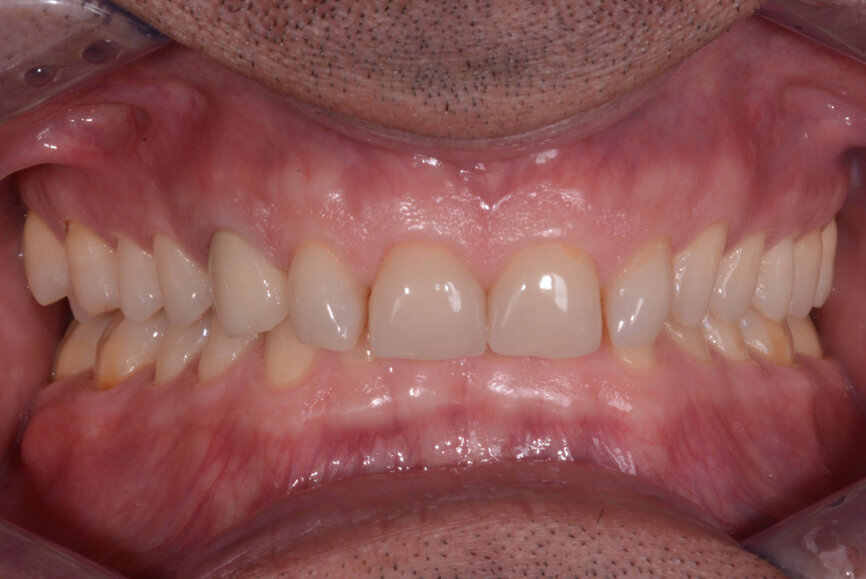

In 2015, a 47-year-old male patient presented complaining of pain in the TMJ. He also had an aesthetic request, since part of the veneer on one of the maxillary central incisors had broken off (Figs. 1–3). The clinical and radiographic analysis (Fig. 4) indicated a loss of bite height and tooth substance due to bruxism.

Fig. 1: Intraoral photograph prior to treatment, frontal view.